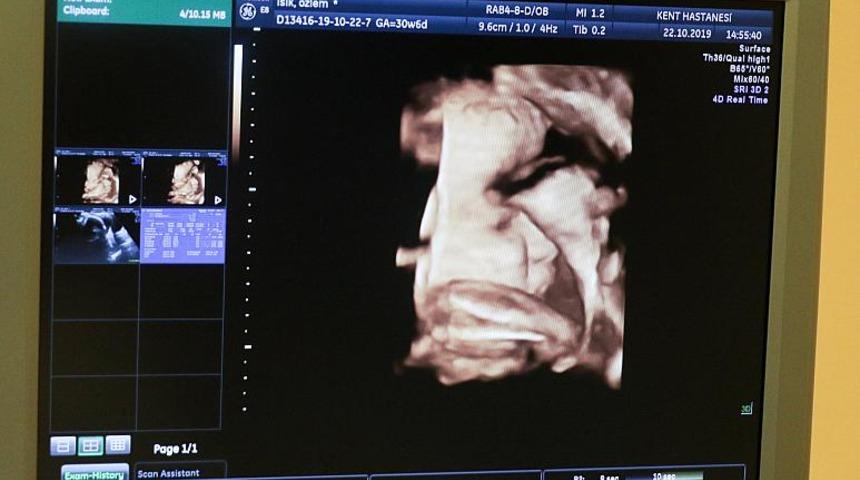

Uzun süre çocuk sahibi olamayan Rebecca Roberts ve 43 yaşındaki Rhys Weaver'ın Noah adını verdikleri ilk bebekleri 7. ve 10. hafta çekilen ultrasonlarda görüldü.

Ancak 12. haftada alınan bir ultrason, Noah'ın beklenmedik bir küçük kız kardeşi olduğunu gösterdi. Ona da Rosalie adı verildi.